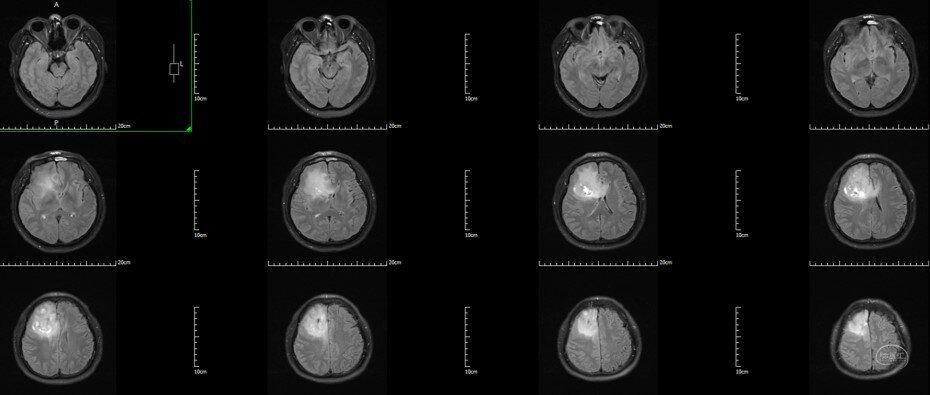

术前T2 Flair:右额-胼胝体-岛叶胶质瘤

术前T2